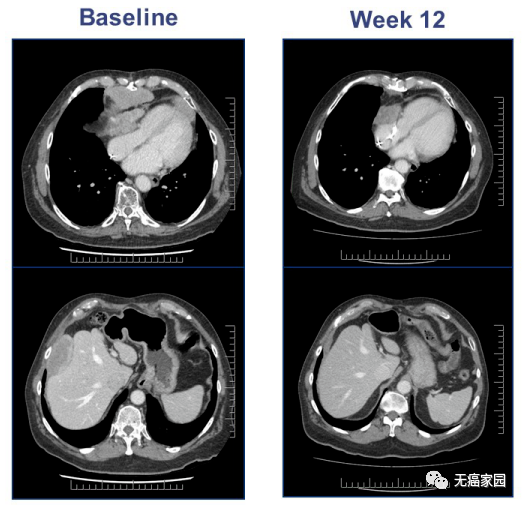

典型病例

一名67岁的老年男性,有4年的滑膜肉瘤患病史,心包复发,既往采用减瘤术和异环磷酰胺治疗,MAGE-A4高表达。输了9.95×109的TCT细胞产品。基线扫描显示很高的疾病负担155mm,疾病在心包和肝脏。输液后扫描,在第12周时,靶向的肿瘤病灶大程度减少了45%。骨髓异常综合征方面在一段时间后继续减少了71%,由于新的不明靶向的病灶的出现,在第24周时发生了疾病进展。